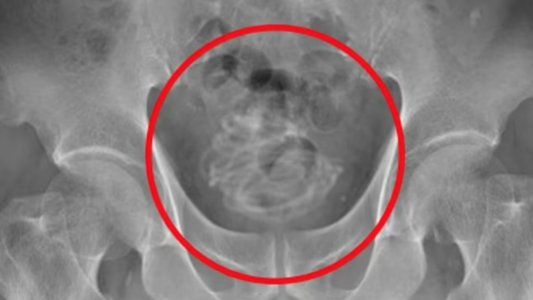

Una tomografía mostró la presencia del objeto en la vejiga del anciano (Foto: Daily Mail).

Los impactantes escaneos publicados por los propios doctores muestran cómo la delgada cuerda, que no tenía manijas, se había enrollado firmemente dentro de la vejiga de este hombre.

Cuando los médicos investigaron su vejiga usando un escáner de ultrasonido, encontraron "un objeto grande acompañado de sombras acústicas" dentro de la vejiga. Luego, una radiografía reveló que este objeto era "un cuerpo extraño enrollado en forma de alambre".